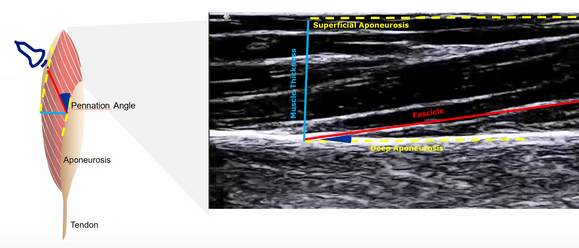

To optimize the utilization of ultrasound for superior data quality, a methodical exploration of current best practices for muscle ultrasound was conducted including validation study with OpenSim arm26 musculoskeletal model during elbow flexion.

To analyze muscle dynamics observed in ultrasound scans, key parameters like pennation angle, location of deep aponeurosis, and fascicle lengths were calculated and compared with OpenSim simulation to get best ultrasound parameters and placement.

B-mode imaging, which tracks muscle structure and fascicle motion

Ultrasound Modalities: Compared B-mode imaging and PW Doppler Imaging for dynamic muscle motion capture. Developed image-processing pipelines in Python using Canny edge detection and wavelet-based feature extraction to convert spectral Doppler velocity traces into time-series signals.